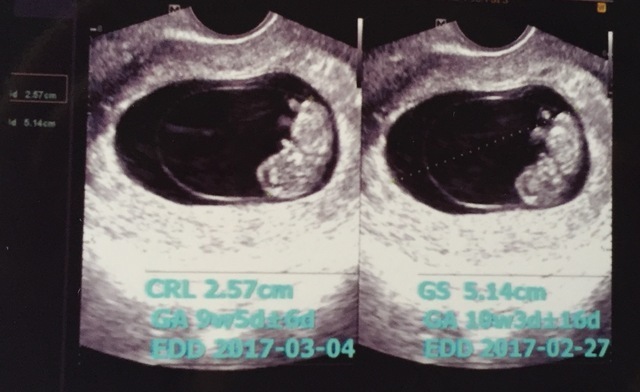

9週0日(9w0d・男の子・双子)|なおねこ さん(29歳)

エコー写真撮影時のエピソード:

妊娠9週目で双子と明らかに分かった写真です。

双子が欲しいと思っていたのでとてもびっくりしたし、初めての妊娠でびっくりと不安が入り混じった心境でした。また、病院も紹介された大学病院での初診だったのでとても緊張しました。